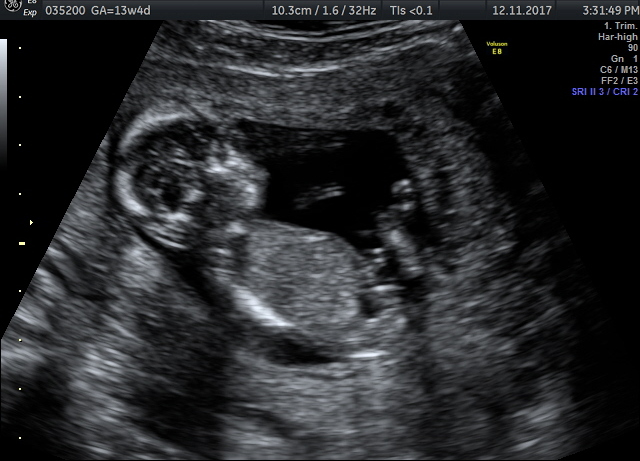

Please check my 13th week nt scan images and help with me the gender of my baby...Attachment 38201

anyone have any idea ??